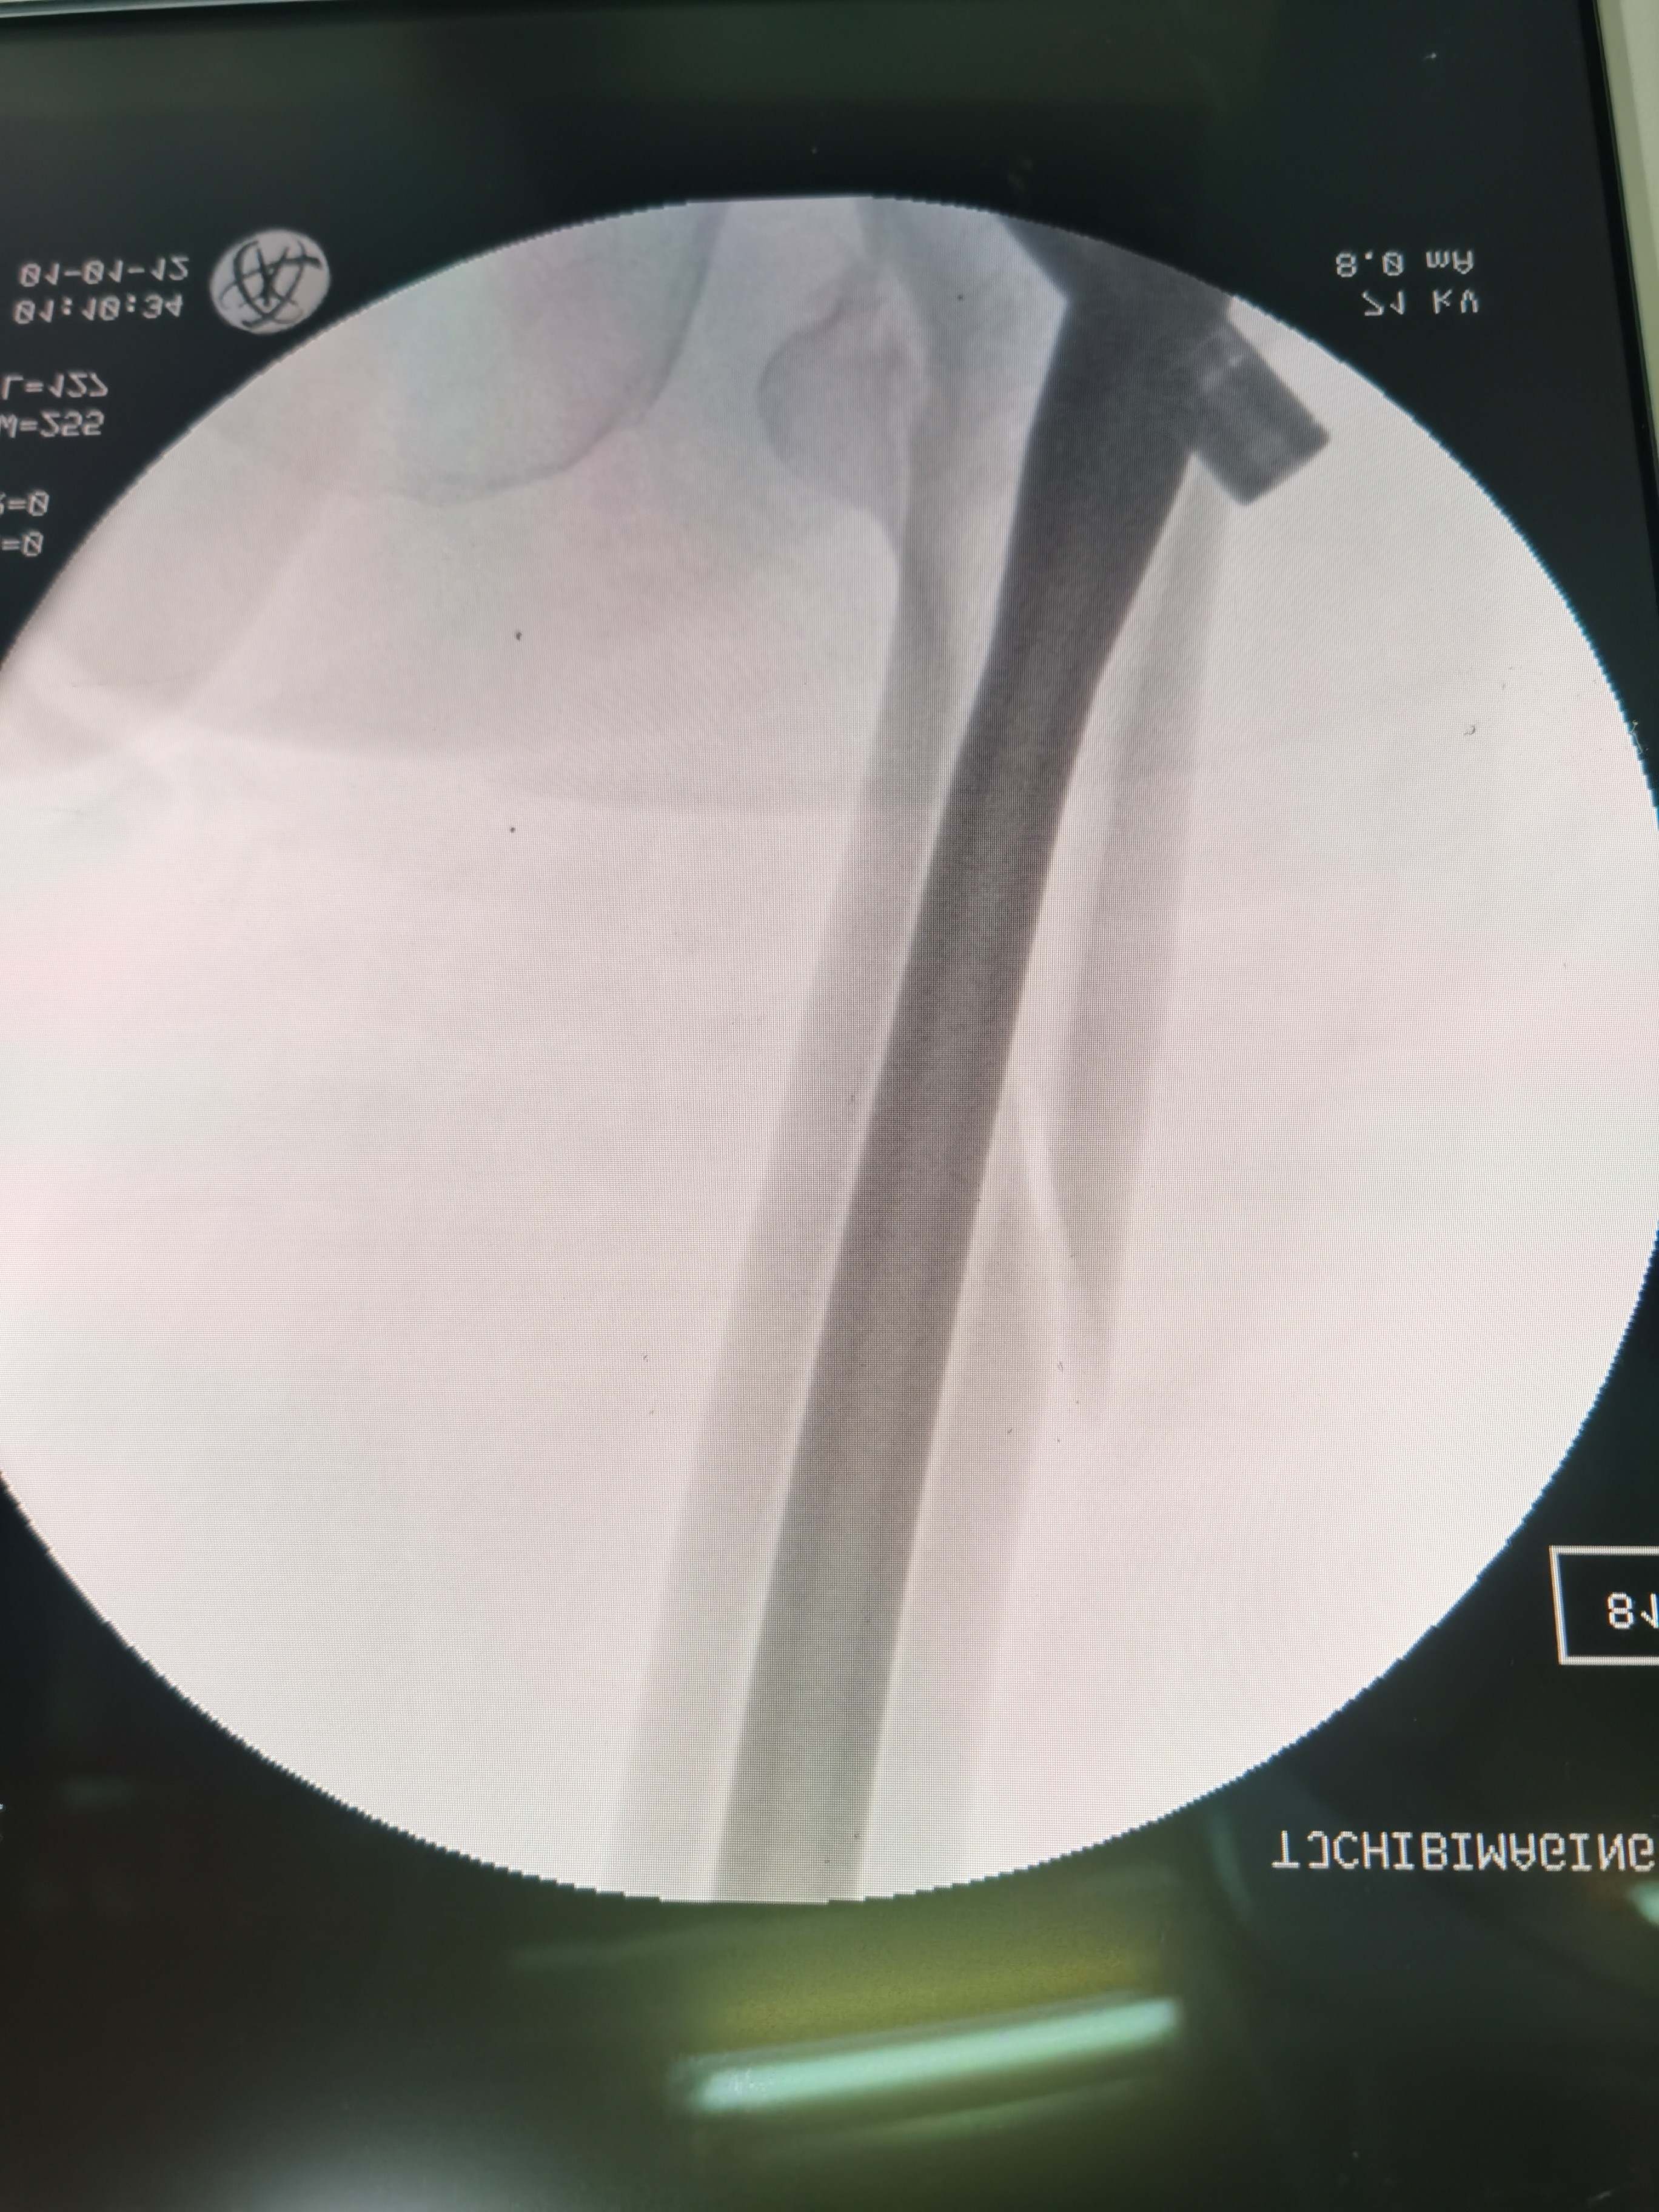

骨外狂徒张三 等 4 位达人已点赞65岁男性患者,摔伤致左股骨近端粉碎性骨折,完善检查,在没用牵引床的条件下闭合复位,微创植入加长型PFNA髄内钉,术中将术侧臀部略垫高,纵向牵引后一助手维持在内旋位,然后按流程手术,整个手术过程顺利,远端锁钉借助瞄准器外架用4.0克氏针盲打,顺利锁入远端锁钉,手术1小时,出血约50mⅠ。

术中透视